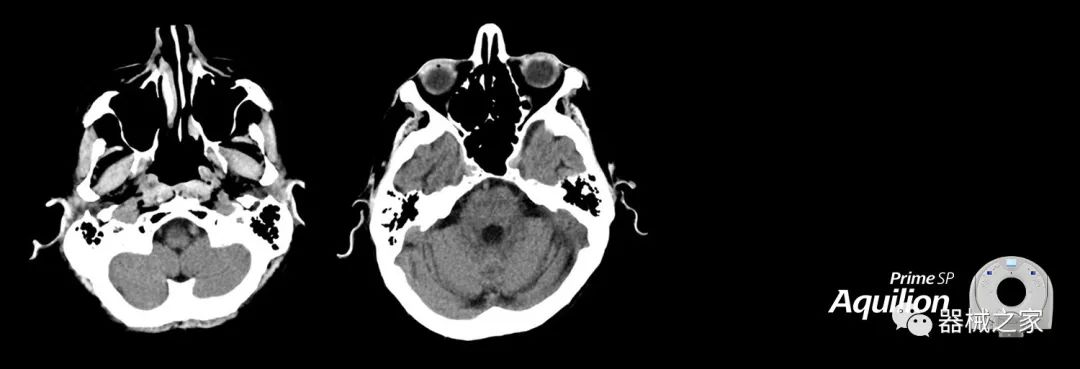

在以患者為中心的放射腫瘤學(xué)領(lǐng)域,計(jì)算機(jī)斷層掃描(CT)的可訪問(wèn)性,可重復(fù)性和靈活性至關(guān)重要。為了建立這些價(jià)值,佳能醫(yī)療系統(tǒng)美國(guó)公司現(xiàn)在正在擴(kuò)大其放射腫瘤學(xué)CT模擬產(chǎn)品,包括Aquilion Prime SP和Aquilion Lightning 80高級(jí)CT系統(tǒng)。除了Aquilion LB之外,Aquilion Prime SP和Aquilion Lightning 80現(xiàn)在還包括放射治療(RT)選項(xiàng),可為腫瘤學(xué)規(guī)劃提供高質(zhì)量的CT成像和精密工具。

擴(kuò)展視野(EFOV)可以看到更多的解剖結(jié)構(gòu)。Aquilion LB采用85 cm EFOV,而Aquilion Prime SP和Aquilion Lightning 70采用70 cm EFOV。

Aquilion Prime SP使設(shè)施能夠處理具有挑戰(zhàn)性的案例,同時(shí)為員工提供快速,靈活和高效的解決方案。